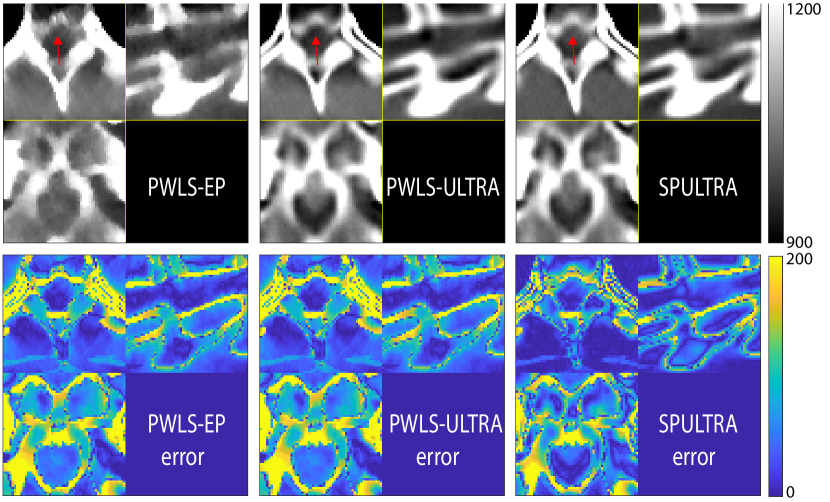

Fig. 4 shows the reconstructed images and the corresponding error images for PWLS-EP, PWLS-ULTRA, and SPULTRA, at and . Compared to the PWLS-EP result, both PWLS-ULTRA and SPULTRA achieved significant improvements in image quality in terms of sharper reconstructions of anatomical structures such as bones and soft tissues, and suppressing the noise. However, the PWLS-ULTRA method introduces bias in the reconstructions, which leads to larger reconstruction errors compared to the proposed SPULTRA method. In Fig. 4, we marked three 3D ROIs in the axial plane, i.e., ROI 1, ROI 2, and ROI 3. Fig. 5 shows the zoom-in images of a 3D plot of ROI 1, and those of ROI 2 and ROI 3 are shown in the supplement. We also plot the evolution of RMSE through the axial slices of the three 3D ROIs in Fig. 6. The figures demonstrate that SPULTRA clearly outperforms the competing PWLS-EP and PWLS-ULTRA schemes.

The above advantages of SPULTRA can be seen more clearly when observing the image profiles. Fig. 7 plots the image profiles for the three methods together with that of the ground-truth image. Fig. 4 shows the horizontal green solid line and the vertical red dashed line, whose intensities are plotted in Fig. 7. It is obvious that the profiles for SPULTRA are closest to the ground-truth among the three compared methods. The gap between the profiles of the PWLS-based methods and the ground-truth shows the bias caused by the compared PWLS methods.

Fig. 14 and Fig. 15 plot the zoom-ins and the corresponding error images of ROI 2 and ROI 3 for the XCAT phantom simulations in Section V.A, with and , respectively. In Fig. 15, we highlighted a region in the axial slice with small red arrows. We show the zoom-ins of the ground-truth ROI 2 and ROI 3 of the XCAT phantom in Fig. 16. The results show that SPULTRA improves image quality over PWLS-EP and PWLS-ULTRA by reducing bias and improving image edges.